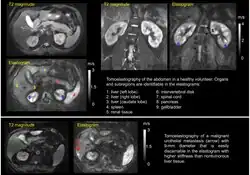

Tomoelastography requires external driver systems, which can efficiently generate shear waves throughout the entire field of view including tissues deep within the body. Multiple drivers can be combined such that waves propagate from the surface into the body from different directions to enable full illumination of larger regions with shear waves. Tomoelastography often employs mechanical vibrations at several driving frequencies for multifrequency wave analysis in order to stabilize inverse problem solutions for viscoelasticity reconstructions. A standard way of multifrequency viscoelasticity reconstruction is based on phase gradient analysis of plane waves[5] whereas other methods employ solutions of the Helmholtz equation.[6][7][8] The feasibility of tomoelastography was first demonstrated in the human abdomen using multifrequency MRE, where it was possible for the first time to display stiffness values (quantified as shear wave speed in m/s) across the entire axial MRI slice.[5] Although the elastograms are quantitative maps, tomoelastography images, like other radiological images, are often presented in standard gray-scale which gives more perceptual contrast to the subtle nuances than the color-scale.

Currently, most applications of tomoelastography are based on MRI, which is why tomoelastography is often referred to as an advanced MRE technique. Multifrequency-MRE based tomoelastography has been used for the diagnosis of diffuse liver disease,[9][10][11] renal diseases such as renal allograft dysfunction,[12] lupus nephritis,[13] and immunoglobulin A nephropathy (IgAN).[14] In addition, tomoelastography has been used for cancer imaging. In the liver, viscoelastic parameters of lesions less than 1 cm in diameter could be quantified for diagnostic purposes.[15] Pancreatic cancer has been shown to be abnormally stiff compared to surrounding tissue, resulting in a large tumor contrast in elastograms.[16][17] In the prostate, tomoelastography has been able to distinguish cancer from benign lesions.[18]